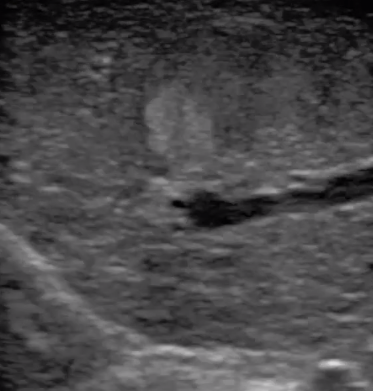

多數(shù)的生殖科醫(yī)生對于受精卵的植入采用憑經(jīng)驗操作或是使用傳統(tǒng)腔內探頭引導,同樣存在手術空間小、受精卵放置位置不確定等風險。專業(yè)的宮腔專用探頭,配合專用的窺器使用,為醫(yī)生提供最大的手術視野。

胎移植臨床圖